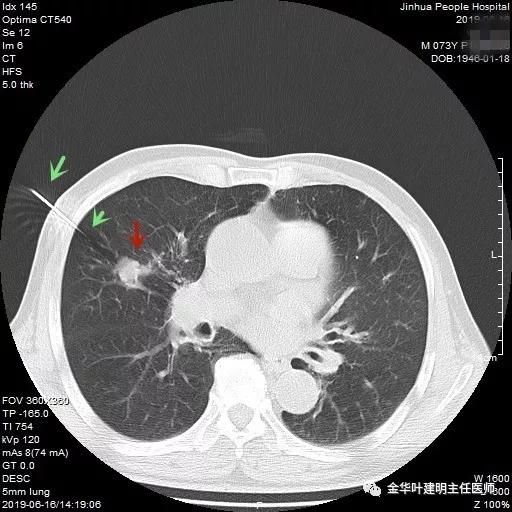

绿色箭头示穿刺针,红色箭头示肿瘤

近日,同事再联系了我,说他同村的吴某已经决定来院接受手术治疗。所以就再次收住入院,予以复查了胸部CT增强,结果如下:

病灶较前有进展,更加膨隆了,直径也有所增加,好在仍未见明显纵隔淋巴结转移(特别肿大的淋巴结,但没有查PET评估)。其肺功能评估情况如下: